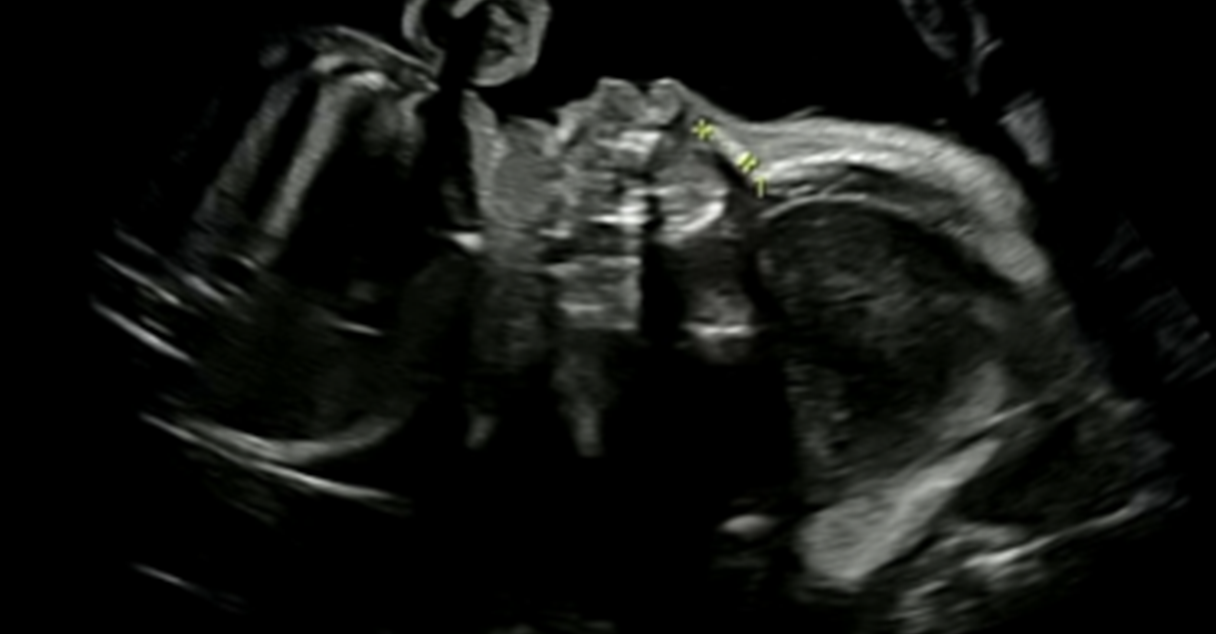

척추

척추도 잘 크고 있는 것을 초음파를 통해 볼 수 있었다.